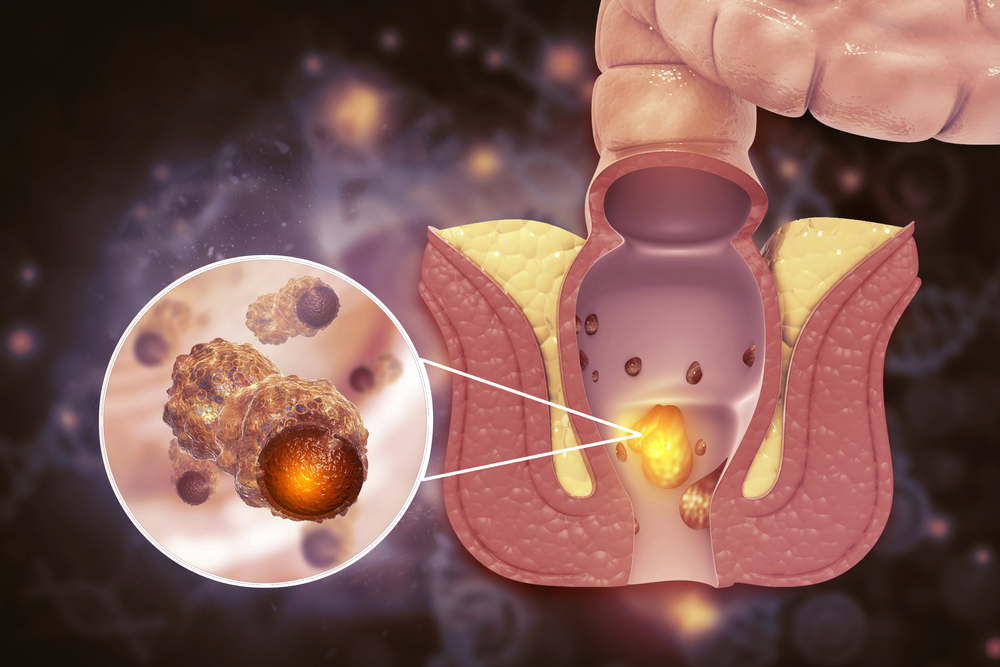

بواسیر چیست؟

بواسیر، در واقع التهاب و تورم وریدهای ناحیه مقعد و انتهای راستروده است که میتواند داخلی (درون مقعد) یا خارجی (در اطراف دهانه مقعد) باشد. این رگها به طور طبیعی در بدن وجود دارند، اما هنگامی که فشار داخل شکم یا راستروده افزایش مییابد، دیواره آنها گشاد و ضعیف شده و به صورت تودههایی متورم ظاهر میشوند.

نقش یبوست در ایجاد بواسیر

در افرادی که به یبوست مبتلا هستند، دفع مدفوع معمولاً با فشار و زور زدن شدید همراه است. این رفتار باعث افزایش قابل توجه فشار در ناحیه لگن و اطراف رگهای مقعدی میشود. در نتیجه، این رگها به مرور زمان کشیده شده، خاصیت ارتجاعی خود را از دست میدهند و متورم میشوند.

همچنین، خشکی مدفوع که یکی از علائم اصلی یبوست است، خود یک عامل مکانیکی تحریککننده است که میتواند با آسیب به بافتهای ناحیه مقعد، زمینه را برای خونریزی و التهاب هموار کند. به همین دلیل است که بسیاری از مبتلایان به بواسیر، ابتدا سابقهای از یبوست درماننشده یا عود کننده دارند.

۱. بواسیر (هموروئید)

یکی از شایعترین پیامدهای یبوست مزمن، بواسیر است. دفع سخت و زور زدن مداوم، باعث تورم و التهاب رگهای ناحیه مقعد میشود. این وضعیت با درد، خونریزی و احساس ناراحتی هنگام اجابت مزاج همراه است و در صورت پیشرفت، ممکن است به جراحی نیاز داشته باشد.